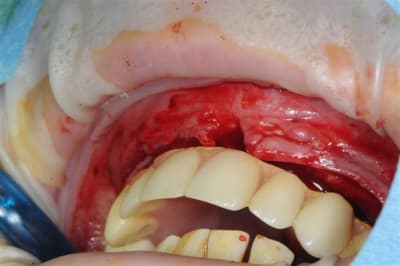

je peux enfin confirmer que la greffe biobank, autorise l'expansion en deuxième intention.

même si je n'ai pas fait un super bombé vestibulaire je me suis permis de faire un mini expansion de crête en particulier sur 22

os magnifiquement vascularisé! excellente adhérence du greffon.

Concernant la résorption du greffon, même constatations que Growler: aucune, les seuls zones qui ont fait reculer la date d'intervention, de 2 mois sont des zones de jonction avec l'os du patient qui avait du mal à fusionner car trop fin au départ (moins d'un mm)je pense.

l'expansion en 22 à la jonction greffon os propre, faite à l'ostéotome manuel, malgré la non approbation de Thomas, c'est parfaitement passée, et nous avons constatés la parfaite liaison du bloc.